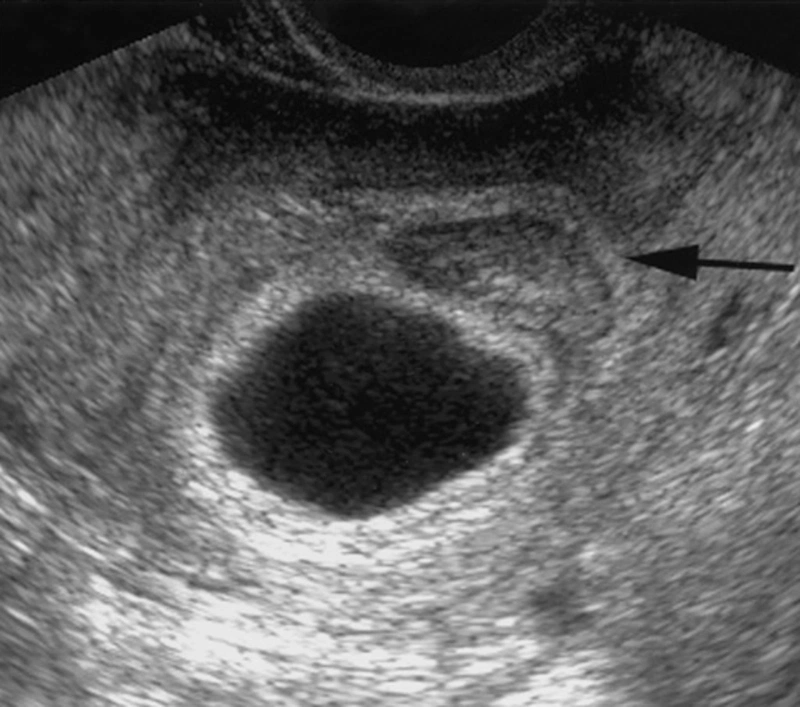

Thông thường, từ tuần thứ 5 đến thứ 6 của thai kỳ, siêu âm thường cho thấy yolksac và phôi thai. Tuy nhiên, thai 5 tuần chưa có yolksac chưa có phôi có sao không?

Yolksac còn được gọi là túi noãn hoàng là cấu trúc đầy đủ đầu tiên của thai nhi. Nó xuất hiện khi trứng được thụ tinh thành công và phôi di chuyển vào tử cung để bắt đầu quá trình phát triển. Túi noãn hoàng đóng vai trò quan trọng trong giai đoạn này.

Trong những tuần đầu thai kỳ, yolksac xuất hiện để chuẩn bị cho sự phát triển của nhau thai. Từ tuần thứ 3 đến 4, nó cung cấp dinh dưỡng để hỗ trợ sự phát triển của phôi thai.

Vậy thai 5 tuần chưa có yolksac chưa có phôi có sao không? Theo chuyên gia y tế, trường hợp mẹ bầu ở tuần thứ 5 với yolksac mà chưa có phôi là khá phổ biến. Sự hình thành của phôi thai phụ thuộc vào điều kiện sức khỏe và sự phát triển riêng biệt của từng bào thai.

Theo các nghiên cứu, quá trình yolksac phát triển thành phôi thai thường mất từ 1 đến 2 tuần, và thời gian này có thể khác nhau đối với mỗi người. Thông thường, phôi thai bắt đầu hình thành từ tuần thứ 6 - 7 của thai kỳ. Đồng thời, nếu phôi thai quá nhỏ, máy siêu âm có thể không nhìn thấy nó. Chỉ khi phôi thai đạt kích thước 2mm trở lên, nó mới có thể được phát hiện qua siêu âm.

Vì vậy, đối với các mẹ bầu ở tuần thứ 5 mà yolksac chưa có phôi, có thể là do phôi chưa hình thành hoặc quá nhỏ. Trong trường hợp này, các bác sĩ thường đề xuất siêu âm lại ở tuần thứ 7 để kiểm tra phôi thai và lắng nghe nhịp tim.